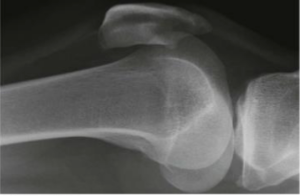

What is this and what type of scan

normal knee, x-ray

fat fluid level, x-ray